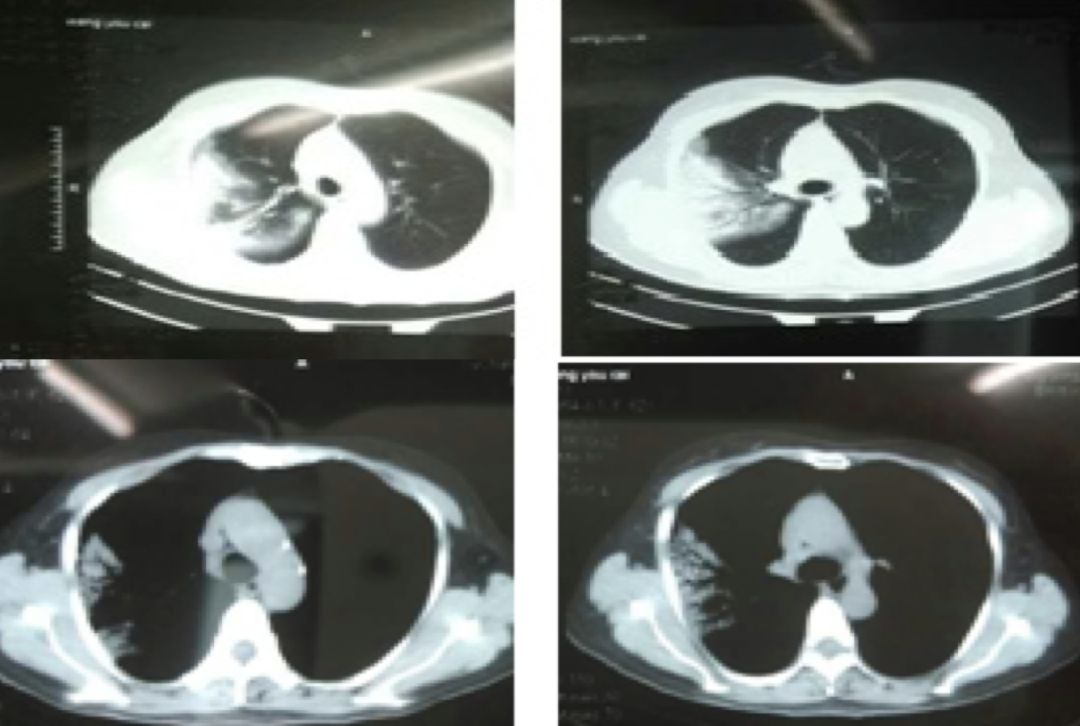

胸部CT:

2017-1-15

2017-1-23

2017-2-5

2017-3-5

患者起病时2017-1-15胸部CT病变主要在右肺上叶后段,表现为大片状高密度影,可见支气管气象,提示支气管内不是阻塞性病变,病灶内有实变,周围有渗出性改变,纵膈窗和肺窗差别比较大,说明病灶密度不是非常高;

2017-1-23胸部CT病灶从范围来看是逐步扩大的,仍可见支气管气象,周围渗出更加明显,纵膈窗来看病灶总体密度增高,影像学表现总体提示病灶进展;

2017-2-5胸部CT:整体病变范围与2017-1-23号CT变化不大,但整体密度呈减低趋势,纵膈窗影像密度与肺窗差别较大,说明病变呈好转趋势;

2017-3-5胸部CT右上肺大片状高密度影消散,仅留下少许高密度条索影,但左肺上叶后段出现新发病变,但与之前右肺上叶病变影像学特征有所不同,之前三次影像学病灶密度是比较均匀的,此次左肺上叶后段病变,除了实变之外可见类空洞样改变,仍有支气管充气征,周围见细条索影,右下肺背段见类结节影像。